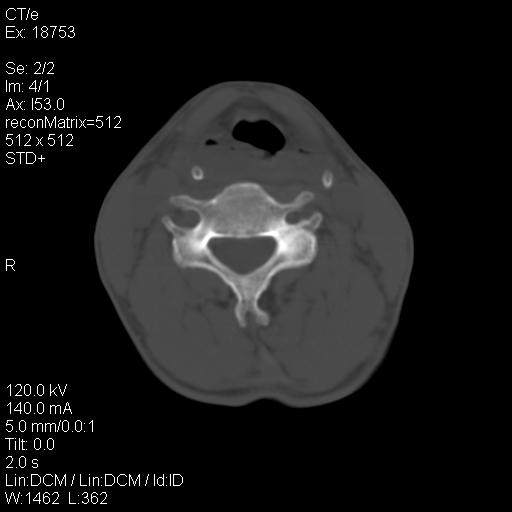

标题: CT21693:男 58岁 右侧咽部疼她2天余 PE:右侧扁桃体肿大 压痛 [打印本页]

标题: CT21693:男 58岁 右侧咽部疼她2天余 PE:右侧扁桃体肿大 压痛

1 弥漫性肿胀,与周围组织分界清晰,发病急,有明显症状,考虑急性炎症【wbc]

弥漫性肿胀,与周围组织分界不清,发病急,有明显症状,考虑:感染性病变!

右化脓性扁桃体炎症伴咽后壁脓肿形成.